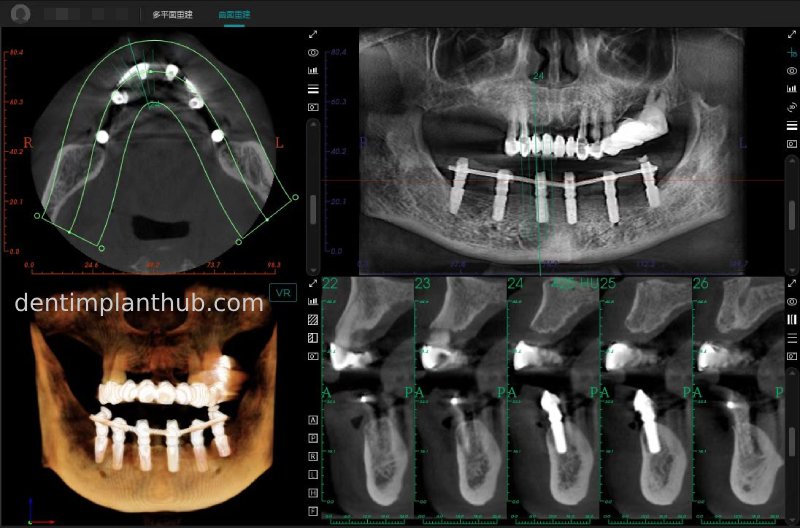

Post-surgical CBCT review photos

16

14

12

22

24

26